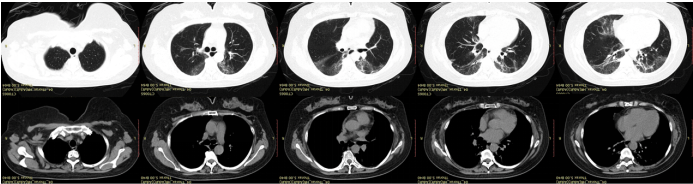

出院后患者继续口服强的松治疗(0.5 mg/kg),4周后(7月28日)复查胸部CT提示两肺炎性病变伴间质性改变,局部轻度支气管扩张,总体较6月30日片稍有进展(图3)。加用他克莫司治疗,嘱其4周后门诊随访。

图片

3  患者胸部CT(2022年7月28日)